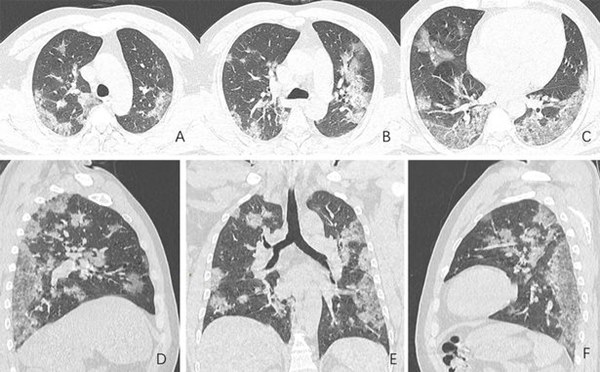

Nó được gọi là hội chứng suy hô hấp cấp tính, ARDS, khi phổi đã chứa đầy chất lỏng. Tình trạng này lộ ra trên phim chụp X-quang: Toàn bộ phổi về cơ bản trắng xóa vì đã ngập chất lỏng. Bệnh nhân mắc ARDS hấp thụ oxy cực kỳ khó. Họ có tỷ lệ tử vong thực sự cao, khoảng 40%. Phương pháp điều trị là phải đưa bệnh nhân vào máy thở. Tạo ra áp lực bổ sung giúp oxy đi vào máu.

Phổi bệnh nhân trông giống như một lớp kính trắng mờ đục, hoặc đôi khi trắng xóa vì nó đã chứa quá nhiều chất lỏng thay vì không khí.

Vấn đề là, khi điều đó xảy ra trong phổi của bạn, chất lỏng và máu dư thừa bắt đầu đổ về. Virus có thể làm tổn thương các tế bào trong thành của phế nang, khiến chất lỏng rò rỉ vào phổi. Một dấu hiệu nhận biết ARDS trên phim chụp X-quang được gọi là “tổn thương kính mờ”, nó giống với những tấm kính cửa sổ nhà tắm kiểu cũ được làm cho mờ đục để không ai nhìn được vào bên trong.

Lá phổi hiện hình như vậy vì chất lỏng chụp lên phim X-quang sẽ có màu trắng, vì vậy, phổi bệnh nhân trông giống như một lớp kính trắng mờ đục, hoặc đôi khi trắng xóa vì nó đã chứa quá nhiều chất lỏng thay vì không khí.